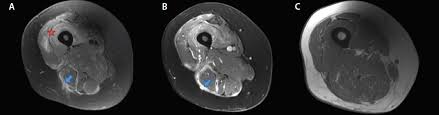

Muscle Histopathology And Mri Of Upper Thigh Axial Sections A D Download Scientific Diagram

Muscle Histopathology And Mri Of Upper Thigh Axial Sections A D Download Scientific Diagram from www.researchgate.net